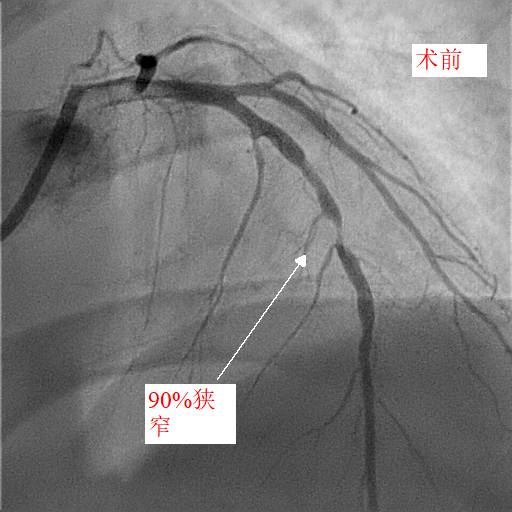

第二天,小天和父亲同一天接受冠脉造影和手术治疗,冠脉造影进一步明确了:小天冠状动脉回旋支完全堵死、前降支90%堵塞,而右冠状动脉也仅有一丝血流通过。造影中医生发现,小天的血管狭窄已经有一段时间,其中的右冠状动脉已经产生了侧支循环。随后医生在患者右冠状动脉里放入了两个支架,恢复了血流。